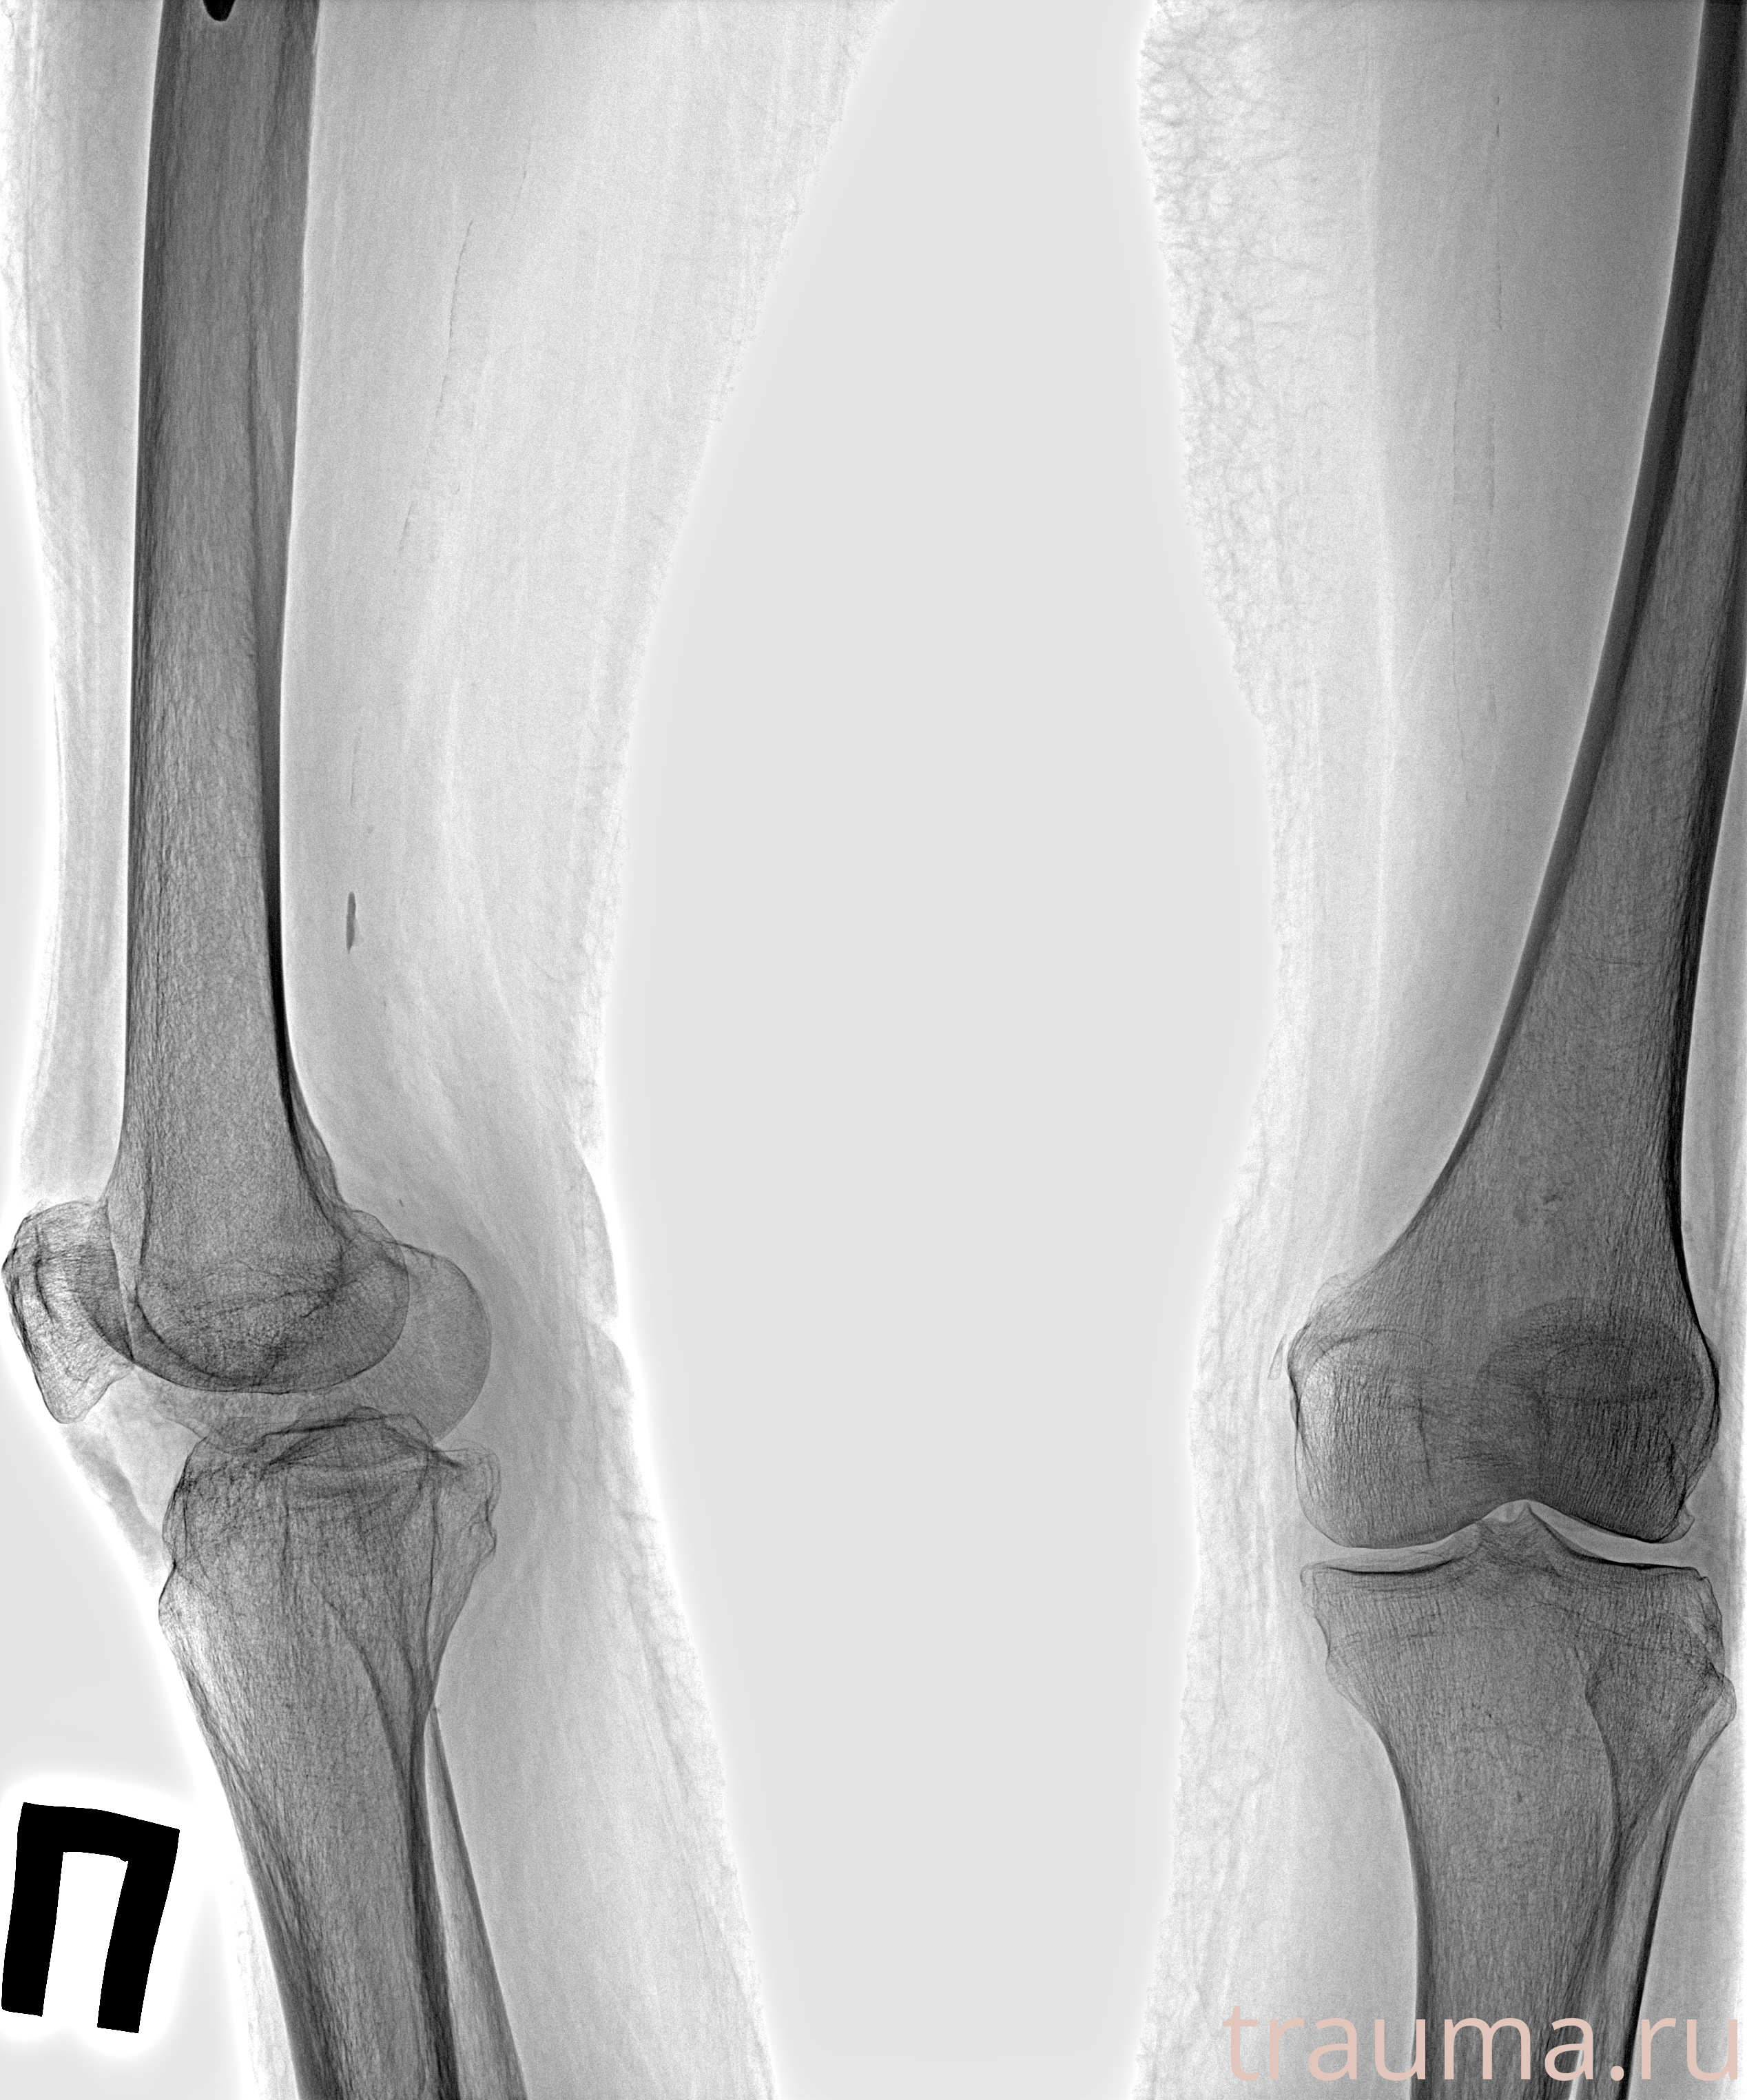

Рентгенограммы

Рентген на дому: по вашему адресу приезжает врач-рентгенолог, травматолог-ортопед с мобильным рентгеновским аппаратом, проводит диагностику травмы или заболевания, делает необходимые рентгенограммы, дает рекомендации по дальнейшему лечению. Получить качественные снимки в домашних условиях возможно благодаря уникальной методике, разработанной МосРентген Центром для института  Склифосовского